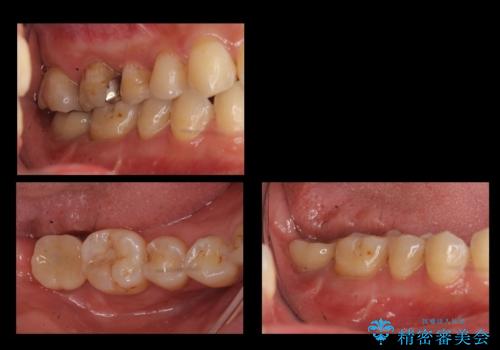

![[ 臼歯部インプラント治療 ]ボロボロになった歯を治療したいの症例 治療後](https://seimitsushinbi.jp/wp/wp-content/uploads/2022/05/c9b3ff0636dc9ea7f888210d13d670bc-500x350.jpg?v=1653278096)